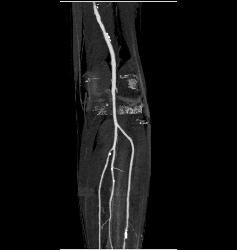

Popliteal Artery With Disease in Trifurcation Vessels- See Full Sequence